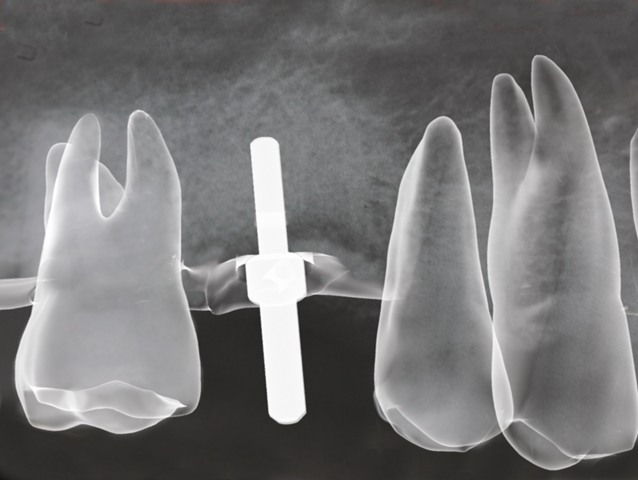

Voraussetzungen und Ablauf Eine wesentliche Voraussetzung für die Implantation ist – neben der allgemeinen Gesundheit – das Vorhandensein von Knochen. Dies kann schnell anhand eines Röntgenbildes ermittelt werden. Ist Knochen in ausreichender Menge und Qualität vorhanden, steht einer Implantation aus zahnmedizinischer Sicht nichts mehr im Wege. Sollte der Knochen an der Stelle der geplanten Implantatposition nicht ausreichen, so wird es notwendig, entweder in einem vorausgehenden Eingriff körpereigenen Knochen an diese Stelle zu verpflanzen oder im Rahmen des Implantateingriffs ein Knochenersatzmaterial zum Aufbau des fehlenden Knochens zu verwenden.

Ist die Implantation erfolgreich verlaufen, dauert es etwa 8-12 Wochen, bis die Implantate fest in den Knochen integriert sind. Dann erfolgt der Zeitpunkt der Freilegung: Die Implantate werden unter dem Zahnfleisch aufgesucht und erhalten durch einen speziellen Zahnfleisch formenden Aufsatz Zugang zur Mundhöhle. Nach ca. weiteren 2 Wochen kann damit begonnen werden, die Implantate prothetisch zu versorgen.